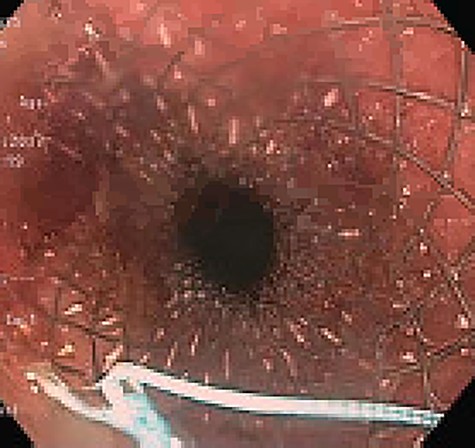

Approximately 2 months into his postoperative course, he returned with symptoms of dysphagia. esophagogastroduodenoscopy (EGD) revealed benign-appearing stenosis at the level of the esophagogastric anastomosis. This was initially dilated with a balloon. However, due to recurrent symptoms, a fully covered SEMS was placed to alleviate stricture (Figs 1, 2). The patient did well for nearly 2 months before returning with recurrent symptoms. A new web was visualized causing complete luminal obstruction (Fig. 3). This was unable to be traversed in antegrade fashion, requiring retrograde access via the jejunostomy utilizing guidewire. A pediatric colonoscope was able to be passed over the guidewire and dilate before subsequent SEMS deployment (Fig. 4). This stent was secured using 2-0 polypropylene suture via Overstitch device (Fig. 5). The initial SEMS was found to have migrated to the mid portion of the gastric conduit. However, due to the small caliber of the proximal stricture and to avoid disrupting newly deployed stent, the initial SEMS was left in place.

Retrograde guidewire, with subsequent pediatric colonoscope and SEMS placement.